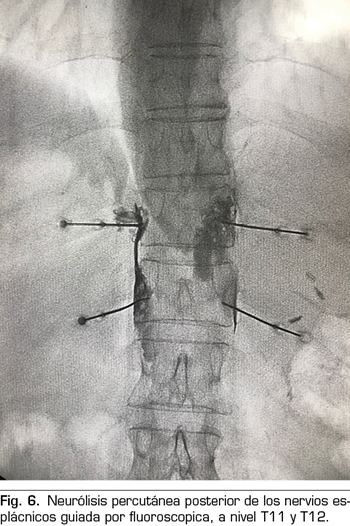

Figura 6